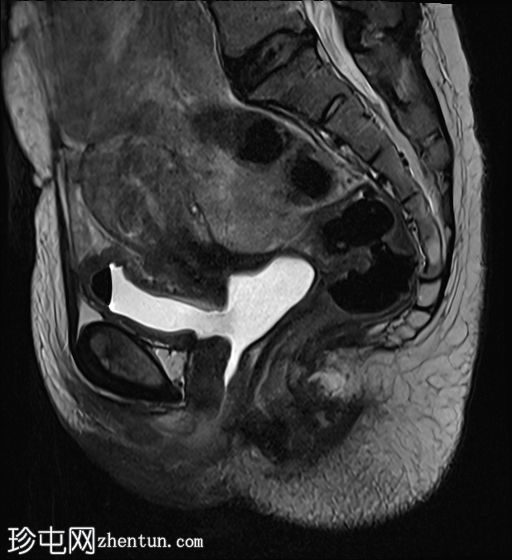

膀胱充盈前

MRI

膀胱后壁与阴道前壁之间存在宽阔的瘘管。膀胱内可见气液平面。

膀胱充盈前,该影像无法显示阴道后穹窿上缘与直肠中段前壁之间较小的瘘管。